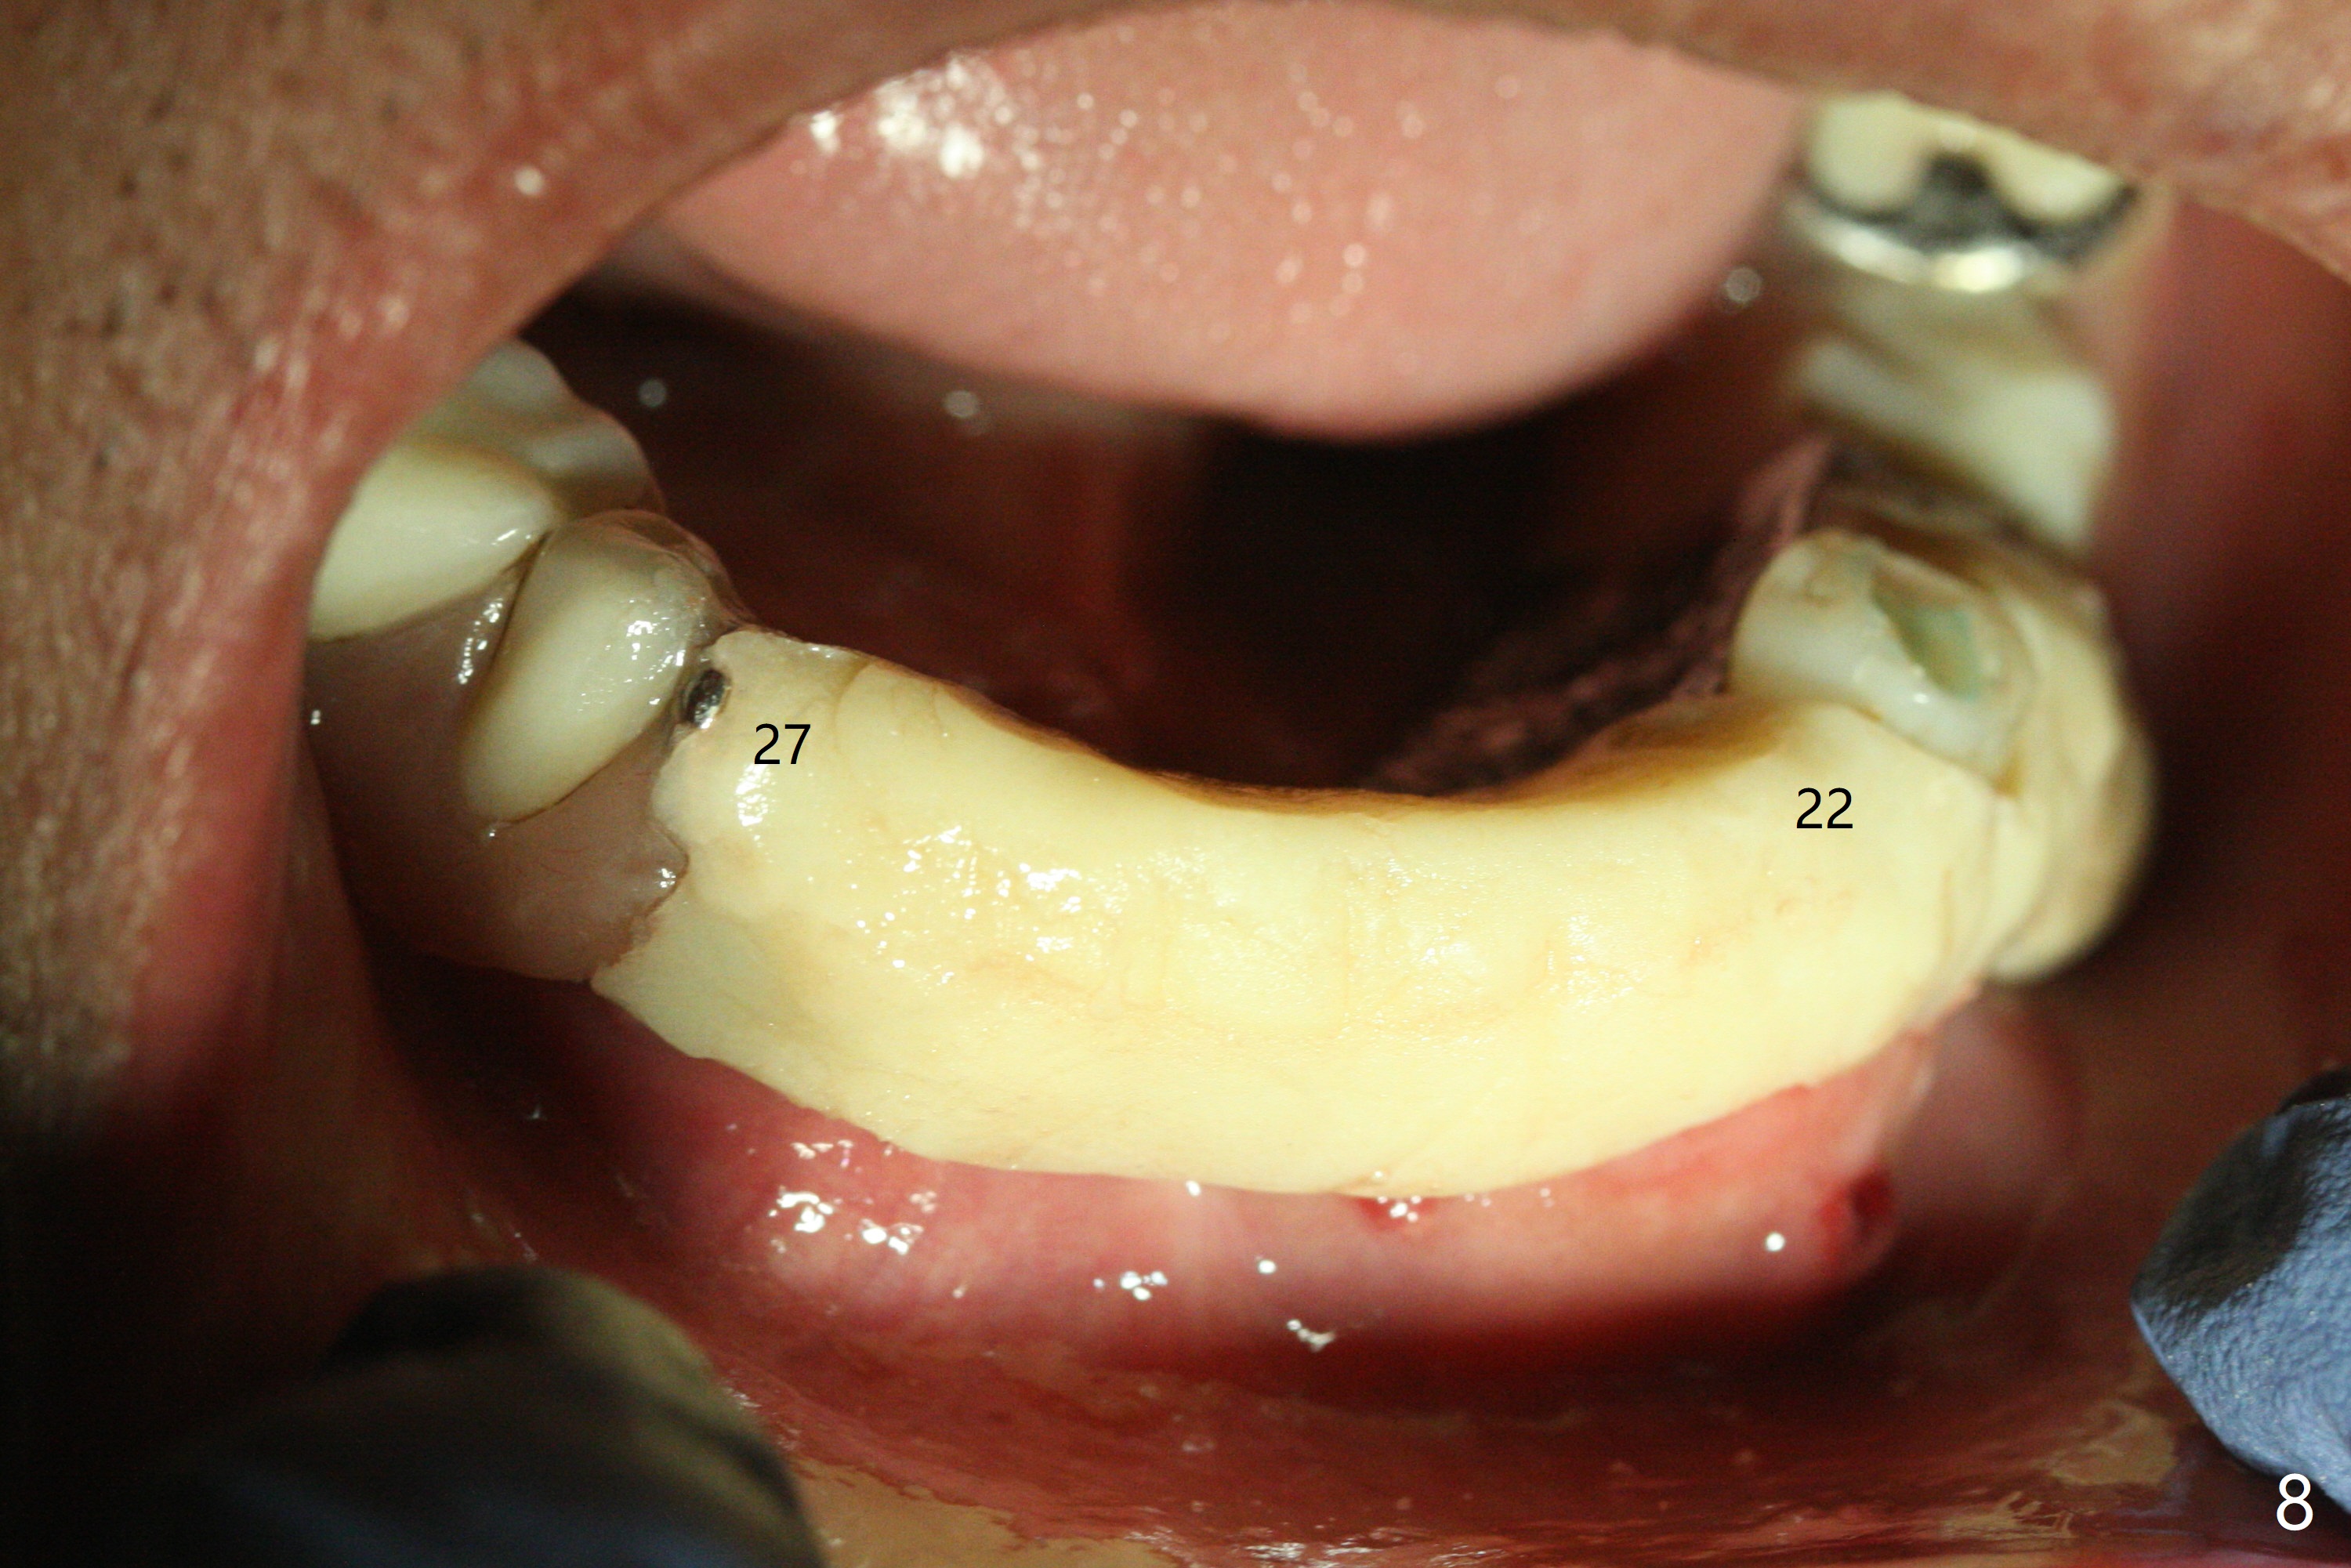

Three months post socket preservation (with buccal plate loss previously), a 3.5x11.5 mm implant is placed at #27 subcrestal (Fig.1). When implants are placed at #22 and 20 (Fig.2,4), threads are exposed buccal (B). Mixture of autogenous bone and allograft is placed to cover the exposed threads (Fig.3,5) following deep placement at #20. For safety, the implant at #20 is buried. Pain control at #18 is poor when initial osteotomy is being established (Fig.6 *), as related to severe infection. Repeated block anesthesia allows to finish implant placement with primary stability; a 3.5x2 mm ball abutment is placed (Fig.7). With placement of 2 other ball abutments at #27 and 22 (Fig.3), the lower existing RPD is converted to a removable provisional (Fig.8). With addition of acrylic, the socket of #20 is covered (Fig.9). There is no apparent bone #20 distal 3 months postop (Fig.10,11 <). Re-graft is needed? The implant at #21 appears immediately subgingival 5 months postop (Fig.12 *). The distobuccal threads are exposed (Fig.13). After decortication, allograft is placed, followed by 6-month membrane. In fact, a shorter and smaller implant should be placed instead. The patient has to wear the RPD for mastication. It would be more painful without it. Later the tissue surface of the RPD is trimmed.